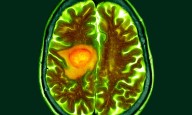

The Elecsys pTau181 test is intended for patients ages 55 and older presenting with signs, symptoms or complaints of cognitive decline. It measures phosphorylated Tau (pTau) 181 protein in human plasma, a key biomarker for Alzheimer's pathology, including amyloid plaque and tau aggregate pathology.